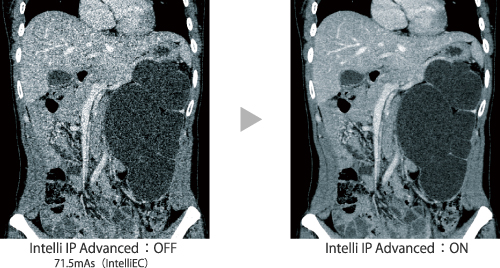

Intelli IP

Intelli IP — итеративная обработка для снижения шума. Отличие Intelli IP (Iterative Processing) от традиционных фильтров изображений заключается в снижении шума путем применения повторной обработки как полученных сырых данных, так и реконструированных данных на основании статистического расчета. Для того, чтобы в каждой области оптимизировать уровень снижения шума, резкость, зернистость и т.п., используется метод итеративного приближения.

Intelli EC

Intelli EC — автоматическая 3D модуляция мА для оптимизации дозы. Первый компьютерный томограф с оптимизацией дозы излучения, основанной на тканевом контрасте.Технология Intelli EC (Exposure Control — контроль дозы) определяет размер пациента на основании данных топограммы и в соответствии с ними модулирует дозу. Кроме традиционного модулирования по среднеквадратичному отклонению (СО), впервые на КТ системах оптимизация контроля дозы осуществляется с помощью СКШ (соотношение контраст-шум).